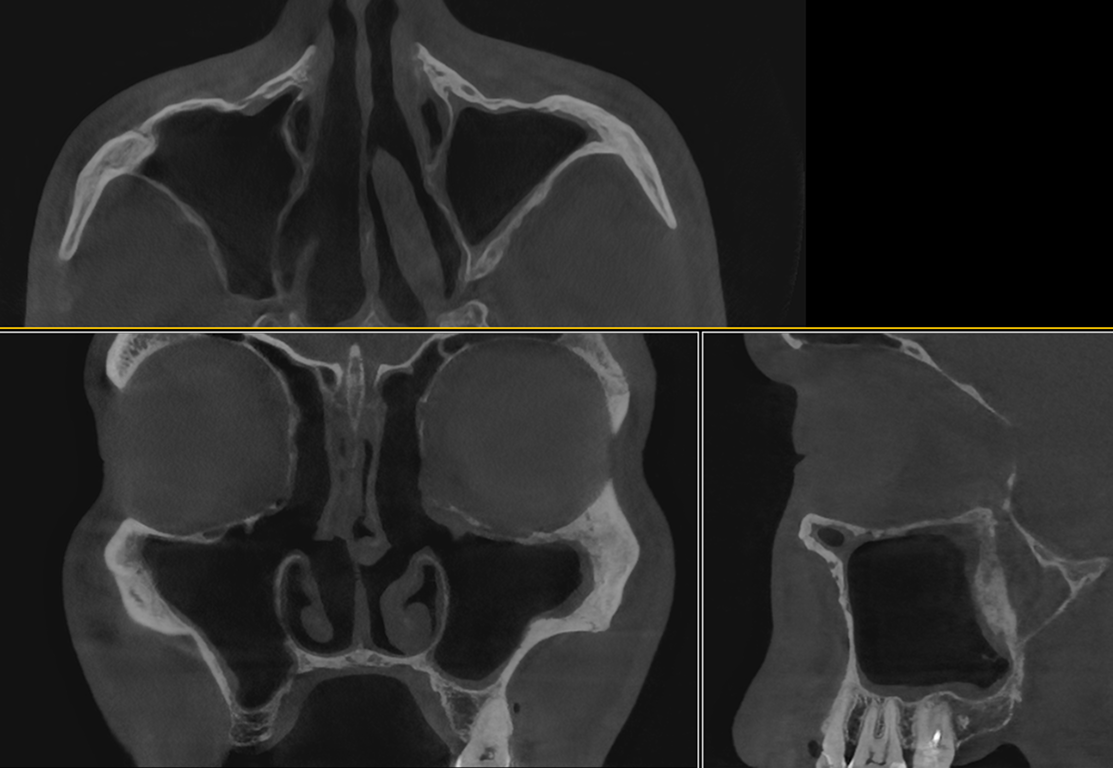

На консультации стоматолог проводит компьютерную томографию верхней и нижней челюстей. Когда стоматолог делает КТ верхней челюсти, на этот снимок также попадают и носовые пазухи. Нередко в них обнаруживаются изменения: киста, воспаление, инородные тела. И задача доктора оперативно направить пациента к опытному ЛОР-врачу, который даст адекватную оценку этим изменениям и при необходимости назначит лечение.

Компьютерная томография до ЛОР-лечения. Хронический риносинусит, полипы. На снимке отмечены пазухи, заполненные полипозной тканью.

Компьютерная томография до ЛОР-лечения. Хронический риносинусит, полипы. На снимке отмечены пазухи, заполненные полипозной тканью, искривленная перегородка носа.